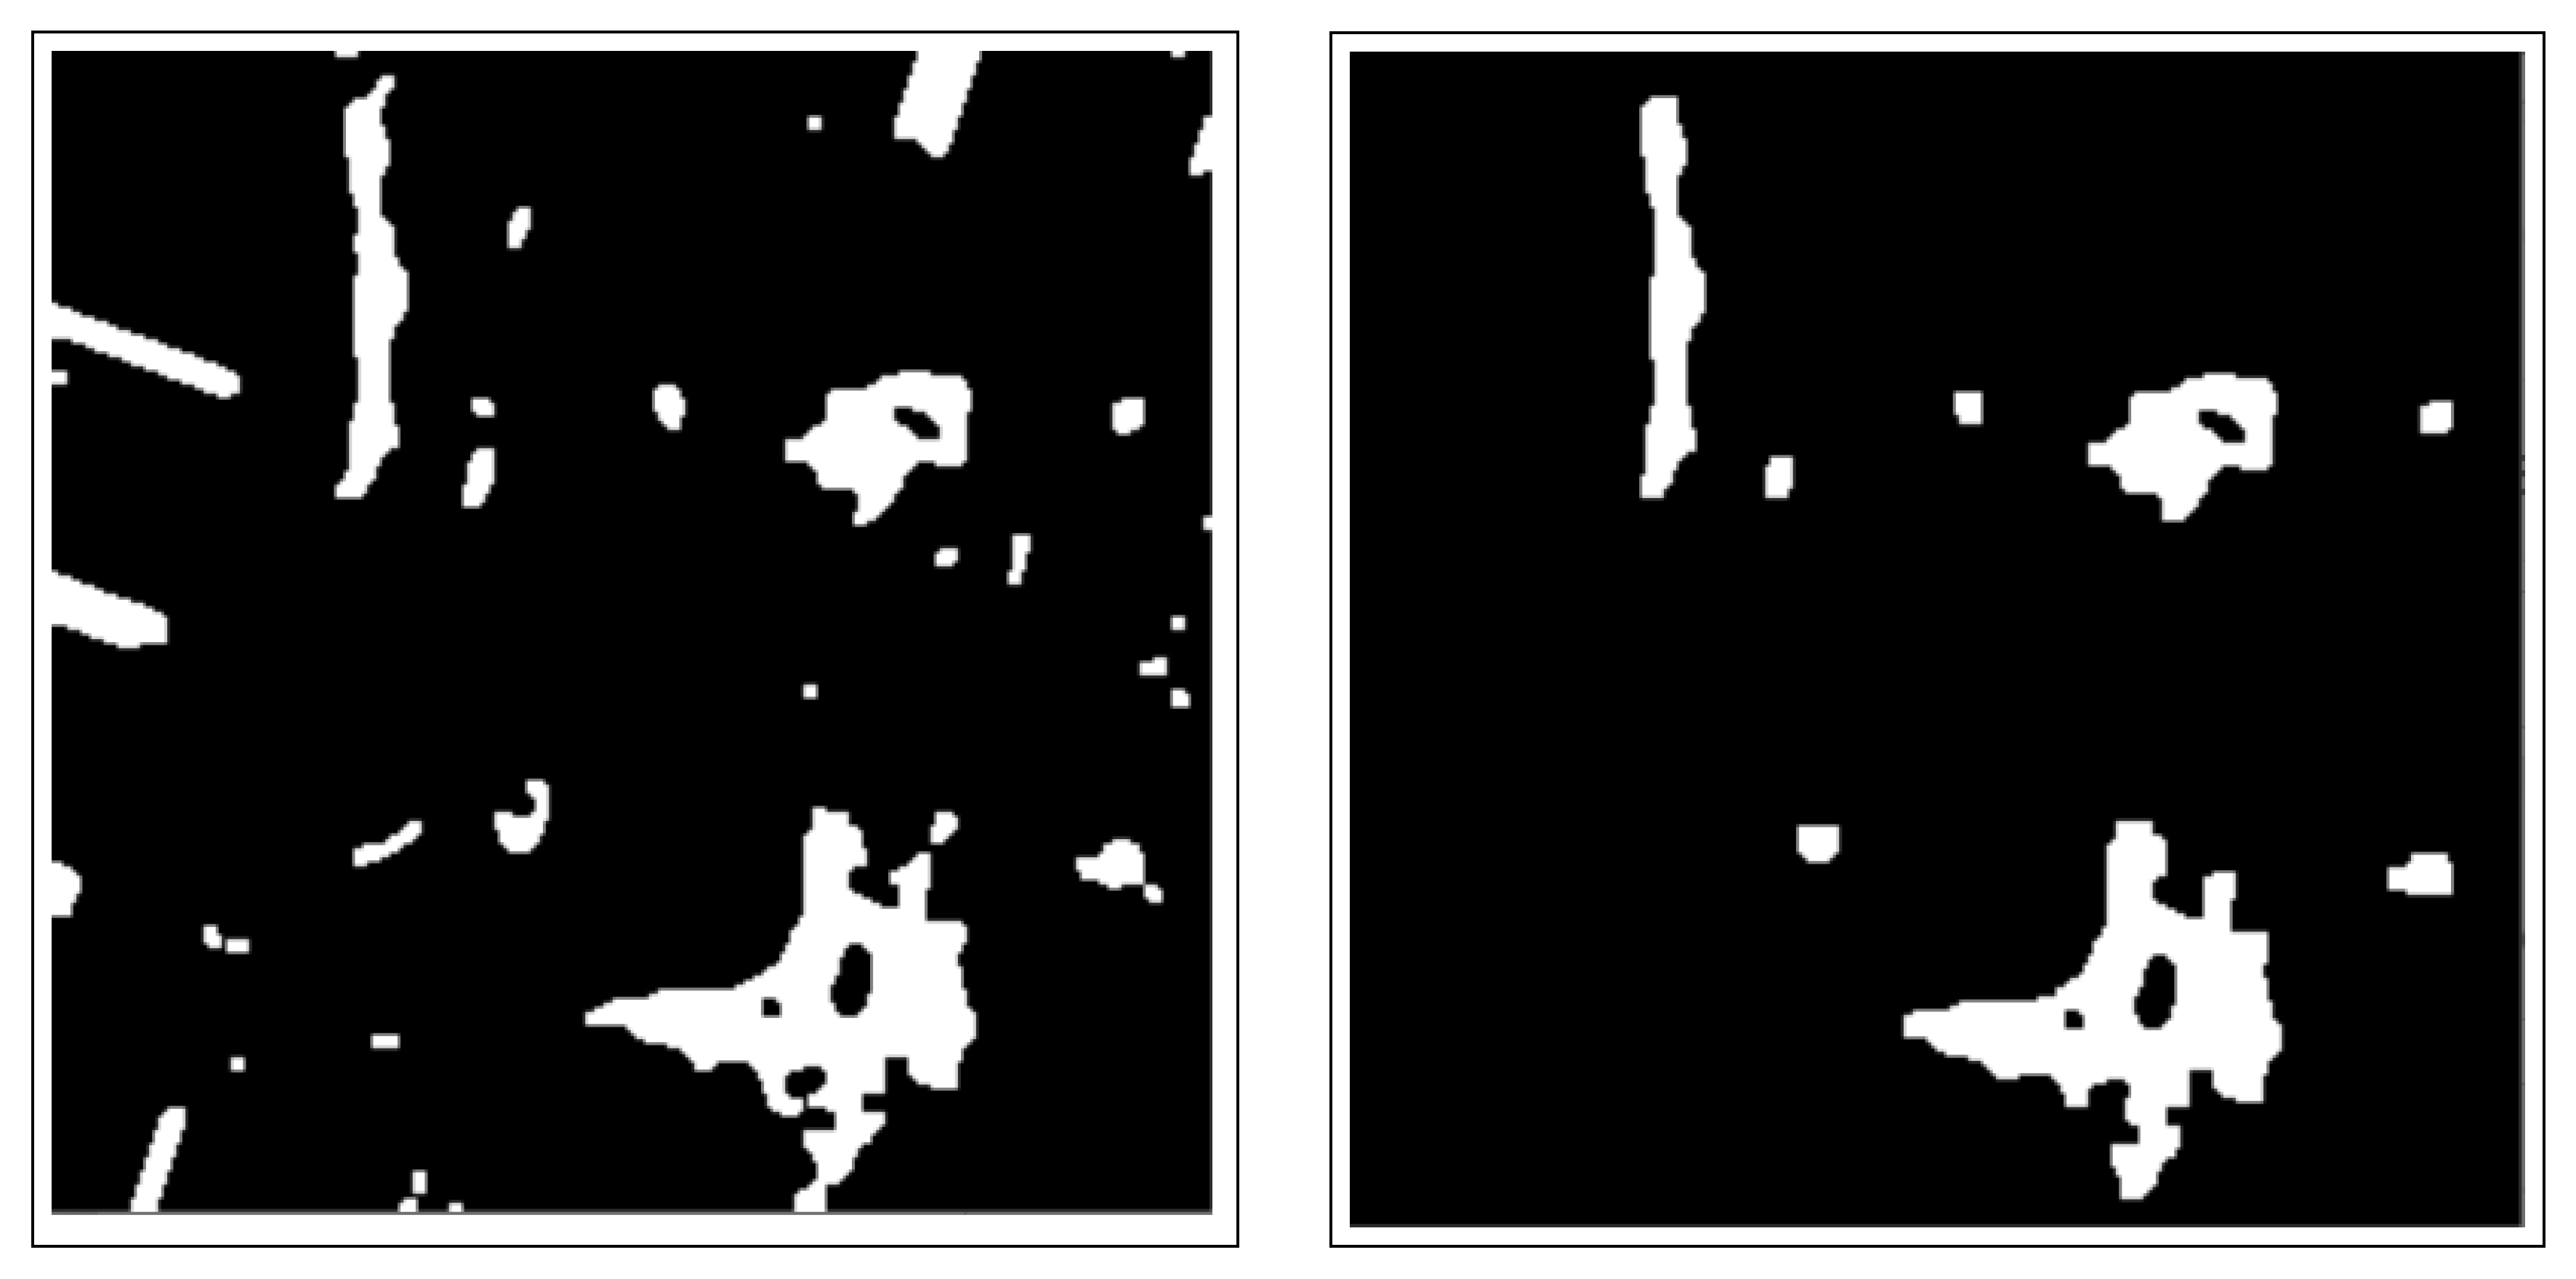

- The use of the connected component analysis method to group components with similar characteristics into binary masks that assist in separating overlapping and non-overlapping objects, thus avoiding over-segmentation.

- The binary masks from the connected component analysis method further aid in addressing the inaccurate segmentation of the image boundaries of intersecting objects, which is common with the active contours method. The proposed method clearly distinguishes the different ROIs from each other, clearly isolating and segmenting the cancerous lesions as visually documented in Section 3 and Section 4.

2.3.1. Connected Component Analysis